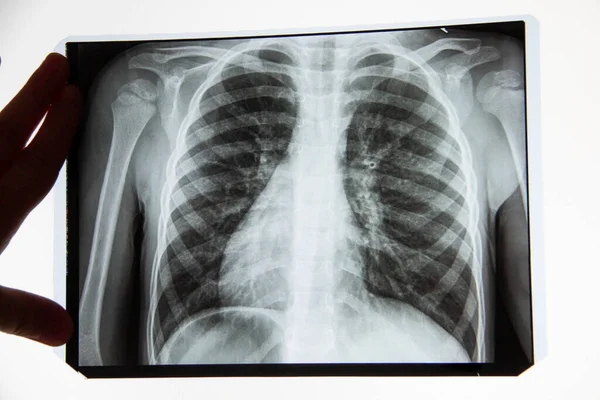

Lung Cancer Screening X Ray

Experience the clarity of Lung Cancer Screening X Ray with our curated collection of comprehensive galleries of images. featuring understated examples of photography, images, and pictures. designed to emphasize clarity and focus. Discover high-resolution Lung Cancer Screening X Ray images optimized for various applications. Suitable for various applications including web design, social media, personal projects, and digital content creation All Lung Cancer Screening X Ray images are available in high resolution with professional-grade quality, optimized for both digital and print applications, and include comprehensive metadata for easy organization and usage. Our Lung Cancer Screening X Ray gallery offers diverse visual resources to bring your ideas to life. Comprehensive tagging systems facilitate quick discovery of relevant Lung Cancer Screening X Ray content. Multiple resolution options ensure optimal performance across different platforms and applications. Time-saving browsing features help users locate ideal Lung Cancer Screening X Ray images quickly. The Lung Cancer Screening X Ray archive serves professionals, educators, and creatives across diverse industries. Instant download capabilities enable immediate access to chosen Lung Cancer Screening X Ray images. Whether for commercial projects or personal use, our Lung Cancer Screening X Ray collection delivers consistent excellence. Professional licensing options accommodate both commercial and educational usage requirements.